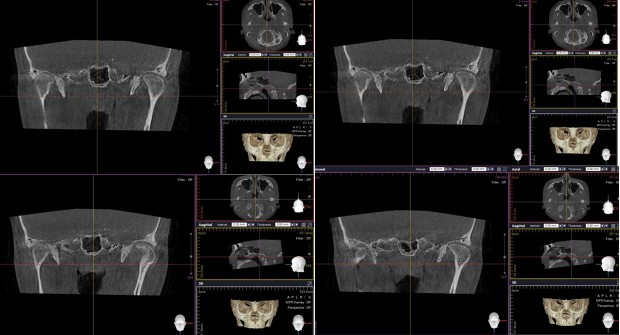

Not long ago, a practicing physician from Prague visited my clinic during orthodontic bracket treatment. She was diagnosed with facial asymmetry and body misalignment, and experienced MCB splint therapy. She was aware that bodily misalignment is related to asymmetry in the facial bones.

There are many around the world—including in Korea—who claim not only to treat TMJ or craniofacial structures, but to treat systemic disorders. Most of them use applied kinesiology for diagnosis and treatment. I myself served for five years as a dental director in a Korean applied kinesiology organization. It is a good discipline. Yet many people—including in Korea—have not gone beyond the level of using applied kinesiology. For example, in the case of the TMJ: applied kinesiology can determine which side of the joint is problematic, and can evaluate how effective a TMJ device is. However, it cannot reveal the direction of asymmetry between the right and left TMJs, or the detailed joint motion. The way to know those is through osteopathic medicine. In Korea, there is almost no practice of osteopathy. 99% of the population do not know the word “osteopath,” and few have experienced osteopathic treatment. It takes a long time to understand the motility of the TMJ.

I have devoted my life to performing orthodontic treatment for people with TMJ problems. Even in the United States, where osteopathy was born and has developed, it seems that almost no one applies the concept of osteopathy when fabricating splints for the TMJ.